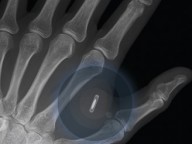

A primeira e mais conhecida é o microchip RFID. Radio Frequency Identification (RFID) refere-se a um sistema sem fio composto por dois componentes: etiquetas (ou tags) e leitores. O leitor é um dispositivo que tem uma ou mais antenas que emitem ondas de rádio e recebem de volta sinais da etiqueta RFID. As etiquetas, que usam ondas de rádio para comunicar a sua identidade e outras informações para os leitores próximos, podem ser passivas ou ativas. As etiquetas RFID passivas são alimentadas pelo leitor e não têm uma bateria. As etiquetas RFID ativas são alimentadas por baterias.

Leia: Coronavírus: novidade no Brasil, implante de chips é aposta da Medicina